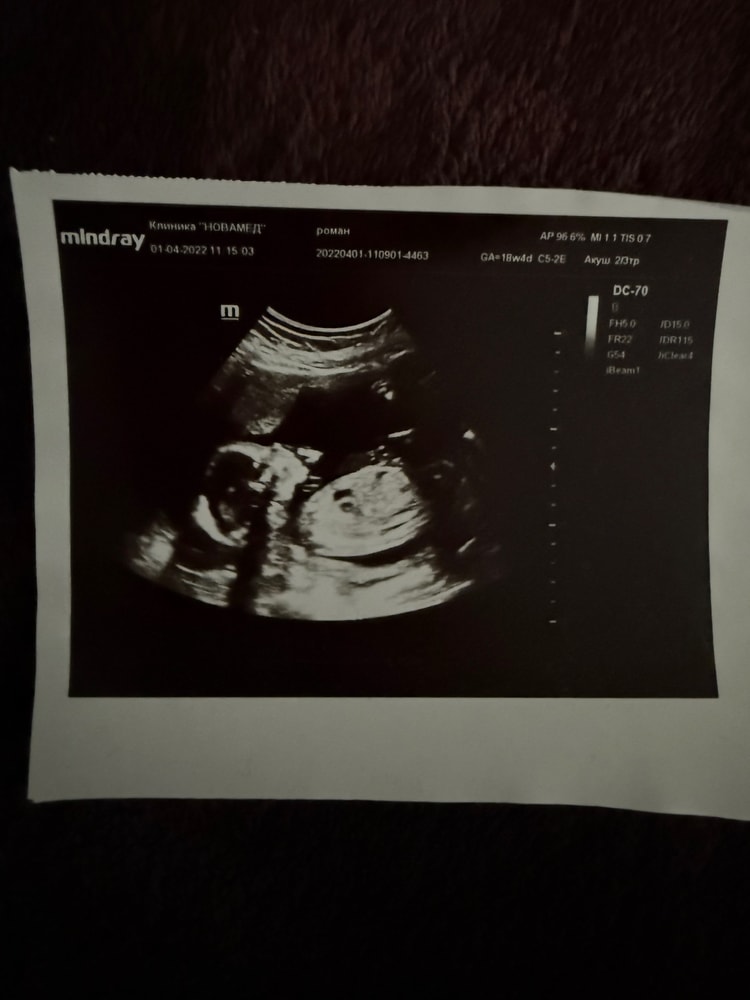

У моего на УЗИ тоже был такой носик, собственно, и родился с таким, очаровательный нос, очень красивый. Я сказала - слава богу, что не как у меня🙈

У меня на таком узи- фото был похож на Караченцева, родился- не похож.

Если вы мечтали о римском ли греческом профиле у ребенка, то к сожалению, такому не бывать)) Он будет похож на вас или вашу родню.

Нормальный, он может и не курносый вообще. Дочка родилась с приподнятым носом-пуговкой, сейчас 2 года и совершенно другой